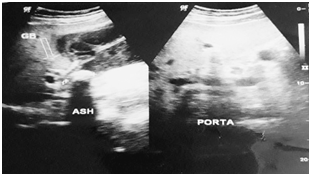

On examination, abdomen was tender and distended with guarding in right hypochondrium (RHC). Soft to firm globular swelling was palpable in RHC which was tender. No other obvious findings were noticed. His pulse rate was 87/min, blood pressure in lying posture was 132/82 mmHg, respiratory rate was 20/min, oral temperature was 98.60F, SPO2 was 99% in room air. Other systemic examinations were normal. Ultrasonography of abdomen revealed features suggestive of chronic cholecystitis with cholelithiasis with thickened gallbladder (~8mm) (Figure 1). Common bile duct was of normal caliber with no echogenic shadow within it. Other abdominal organs were within normal range. Chest X-ray and ECG were also normal. The leukocytosis (13900/cumm) with neutrophilia (86%) was present. Other biochemistry and serology investigations were within normal range. On the basis of history and clinical findings, patient was diagnosed as a case of acute or chronic cholecystitis with cholelithiasis.

Figure 1 Ultrasonography revealed thickened gallbladder with multiple large gallstones with normal porta.

Title: USG of xanthogranulomatous cholecystitis patient.